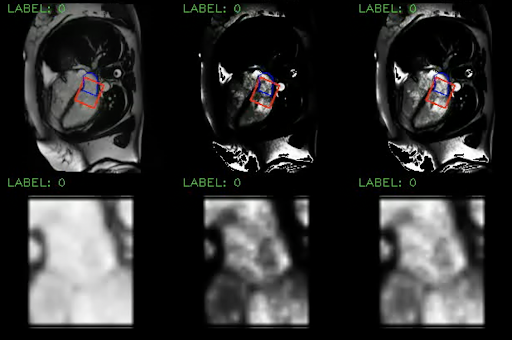

Our CUSSP method consists of five main steps, shown in Figure 4, with the first two steps representing data preprocessing, and the later three steps using network components trained for MR classification, as described in the next section. The pre-processing of the CMR imaging sequence is shown in Figure 8 in the Appendix. We used the segmentation model in 2.1 to locate the mitral valve and the orientation of the left ventricle. We then cropped a square patch with the mitral valve at its center positioned horizontally. After cropping, we applied histogram equalization to the patch with the pixel intensity range of the left atrium. The resulting patches are used by the downstream networks.

Refer to caption

Figure 8: Detailed overview of the pre-processing steps for CUSSP. Top: Example of the 4CH CMR images in the original contrast (left), the left atrium histogram equalized contrast (middle), and the cropped patch histogram equalized contrast (right), with blue contours outline the left atrium, and the red square boxes outline the patch to crop. Bottom: Example of the cropped mitral valve patch as outlined in the red square boxes in the top row.